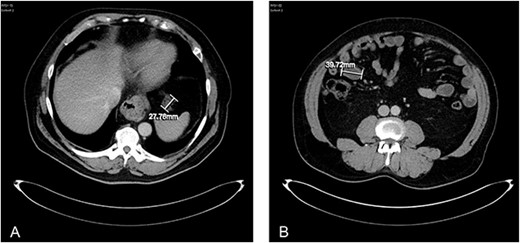

About 1 year later, the patient re-presented for anaemia and underwent a further CT scan. In the right iliac fossa, a 51.96 mm mass was noted such that the appendix could not be visualized separately, with a focus of calcification (Fig. 1). There was infiltration into the adjacent fat and abnormal soft tissue thickening of the peritoneal reflection along the right paracolic gutter. Multiple new peritoneal nodules in the upper abdomen were also identified (Fig. 2). The appearances were in keeping with disseminated malignancy. Following histological analysis, diagnoses of LAMN and PMP was made. The patient was initiated on mitomycin and capecitabine chemotherapy, which modestly reduced the size of the right iliac fossa mass from 51.96 mm to 44.23 mm (Fig. 3).

Axial CT abdomen with contrast demonstrating a peritoneal deposit posterior to the descending colon in the left iliac fossa, measuring 37.15 mm.